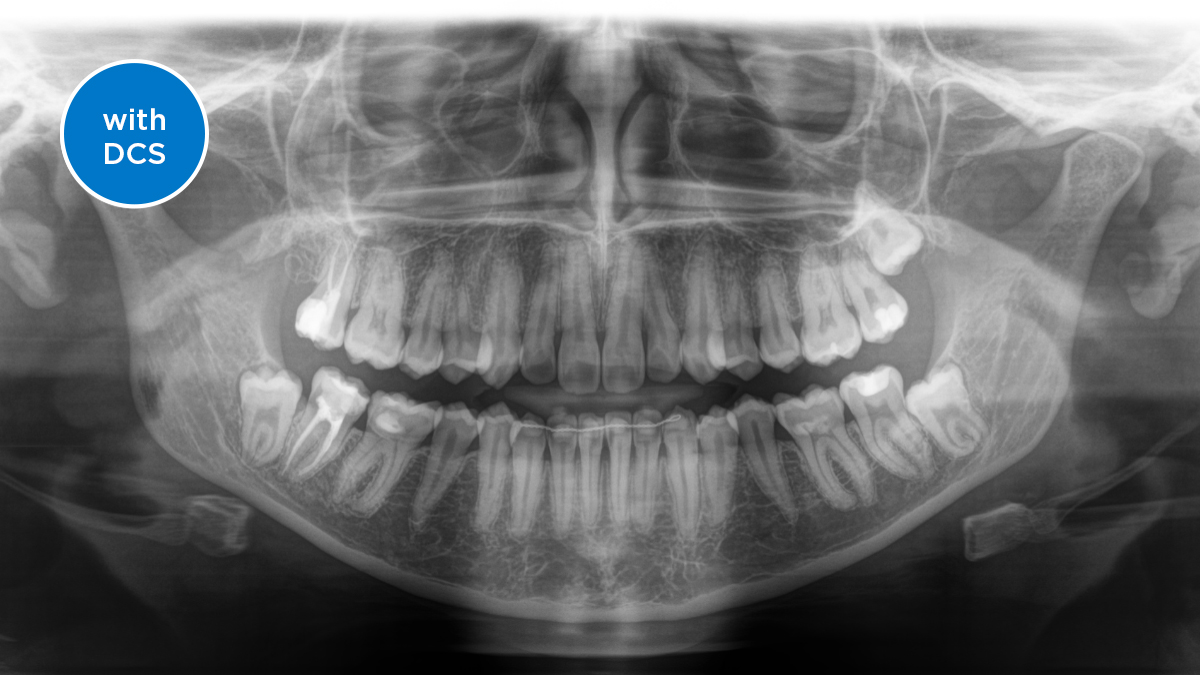

O Sensor de Conversão Direta (DCS) revolucionou o padrão de imagens panorâmicas. Os raios X são convertidos diretamente em sinais elétricos. Assim, não há perda de sinal por conversão de luz, como ocorre nos sistemas convencionais. O resultado: imagens com alto nível de nitidez e contraste, mesmo com baixíssima dose de radiação. Para obter informações de diagnóstico precisas para embasar o tratamento direcionado.

A imagem abaixo mostra uma radiografia panorâmica com e sem a tecnologia DCS. Usando a seta, arraste o controle pela imagem para ver a diferença que o sensor de conversão direta faz na qualidade da imagem e nas possibilidades de diagnóstico.